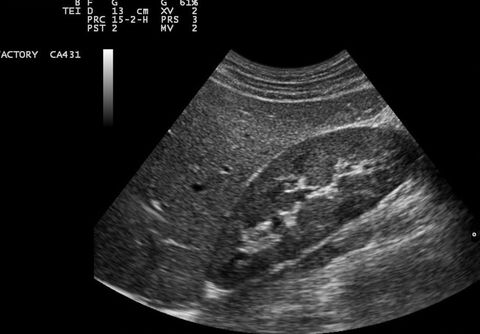

All Obstetrics scans are performed by a highly experienced sonographer who worked at Unversity College London Hospital and Kings college Hospital Fetal Medicine Unit.

All of our sonographers are qualified with diagnostic obstetric and General ulltrasound scanning experience and work within the NHS alongside their role with Ultrasound Partners Ltd.

During your appointment a general well-being check is performed on the baby, in an event of any abnormality being detected, we will discuss this with you and provide a full report for you to forward to your health practitioner.